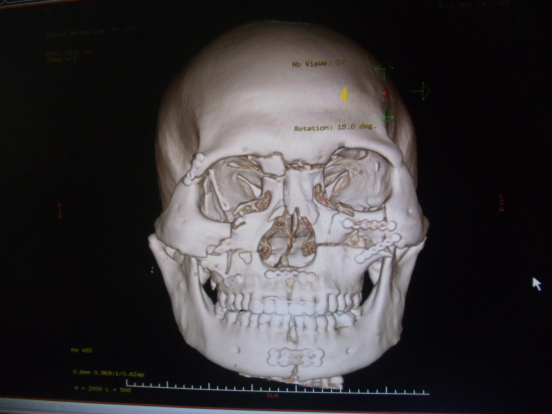

全面部骨折钛板内固定手术